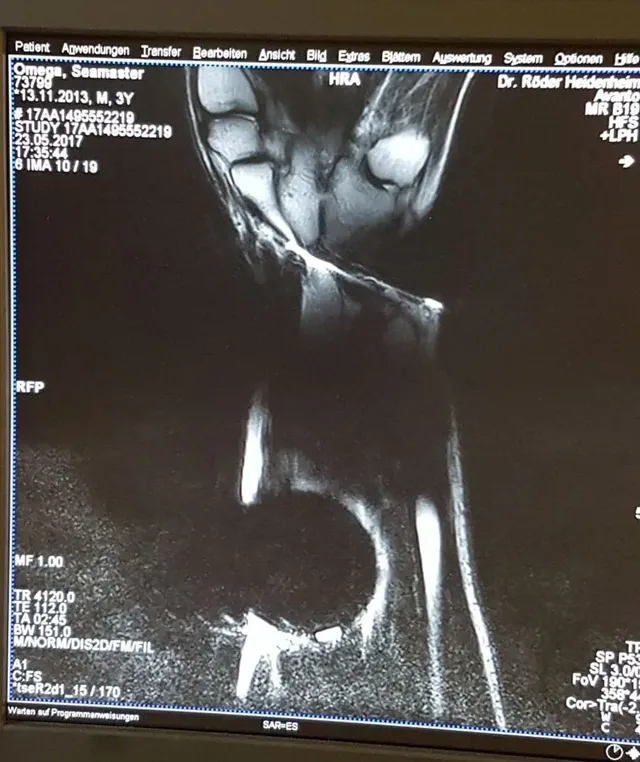

Zunächst kommt sie am Handgelenk ständig in den Randbereich des MRT-Gerätes und damit in ein oft wechselndes Magnetfeld. Dr. Röder vermerkt positiv die geringe Gangabweichung von maximal einer Sekunde am Tag, meistens sogar weniger. Aber dann muss die Uhr selbst ins MRT – auf einer Extremitätenspule und dann am Handgelenk des Arztes. Sie läuft unbeirrt weiter.

UHREN-MAGAZIN testet härter als der Uhrenhersteller

Dr. Röder ist beeindruckt und entwickelt schließlich die Idee, die Taucheruhr in ihrem Medium, also im Wasser, zu "untersuchen" – nicht zuletzt, um Beweisfotos aufzunehmen. "Aber von der Uhr wird man wenig sehen", enttäuscht uns der Fachmann, "weil das Metall eine Signalauslöschung verursacht." Das kenne er von medizinischen Implantaten aus Titan wie Hüftgelenksprothesen.

Omega-Seamaster-Planet-Ocean-im-MRT

Die Omega Seamaster Planet Ocean im MRT © PR

"Wir werden aber beweisen", fährt Dr. Röder fort, "dass es die Uhr auch zentral im Magnet, in einer Spule mit geschalteten Messsequenzen und starken Gradienten-Feldern, die im Millisekundentakt wechseln, aushält. Wenn das klappt, sind wir die ersten, die so etwas zeigen." Wie der Test ausgegangen ist und alles weitere über Magnetfeldschutz bei mechanischen Zeitmessern erfahren Sie im kostenlosen Webinar "Ask the Expert"!